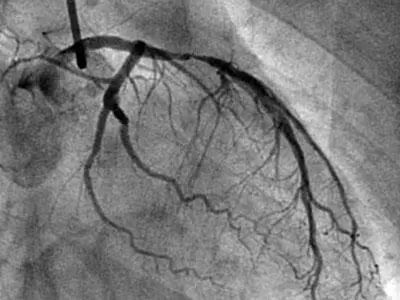

冠脉造影是直接透视下,通过不同角度视察心脏血管的情况,医生更直观地从不同角度来看心脏的各个血管的狭窄情况和程度,相对来说比较准确。

冠脉造影,是需要把导管通过手腕或大腿根的血管,送入到心脏的血管开口,随后再把造影剂通过导管推入心脏血管,造影剂进入心脏血管的同时,立即透视,在X线下就能看到即时的心脏血管影像,也就能看到心脏血管有没有狭窄,以及狭窄的程度。